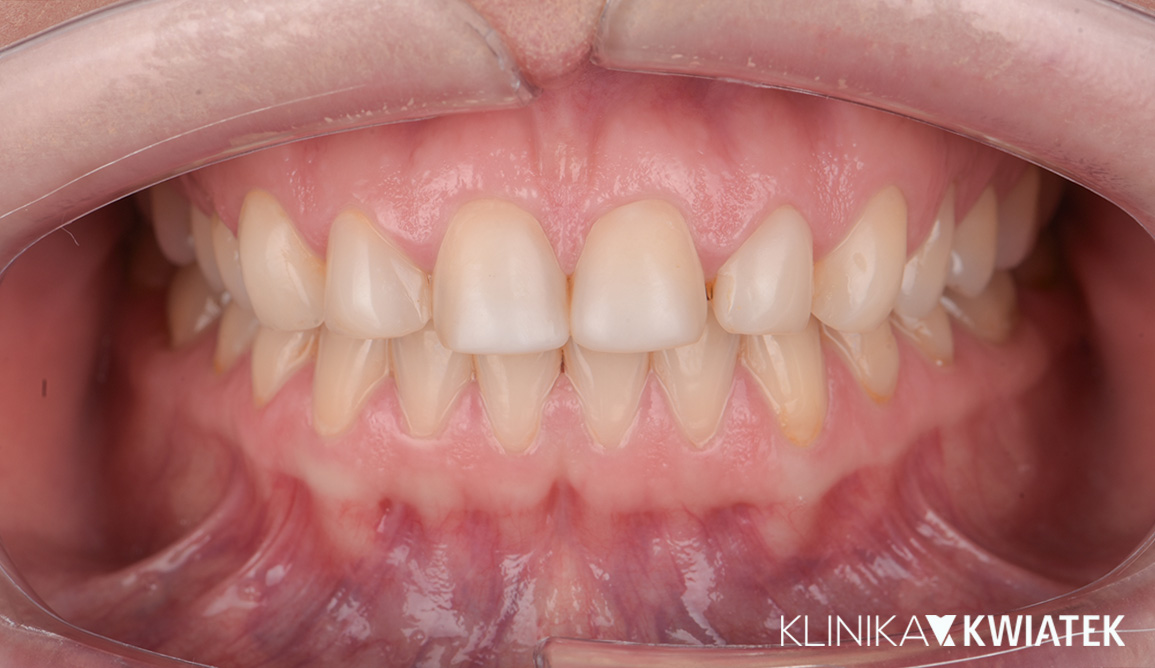

Kompleksowa transformacja uśmiechu po leczeniu ortodontycznym

Pacjentka zgłosiła się do kliniki po zakończeniu leczenia ortodontycznego nakładkami w innym gabinecie, w celu odbudowy brakującego zęba trzonowego. Po szczegółowej diagnostyce zaplanowano leczenie implantologiczne, protetyczne oraz periodontologiczne. Dzięki precyzyjnej pracy zespołu specjalistów uzyskano pełną odbudowę estetyki i funkcji – naturalny, harmonijny uśmiech oraz zdrowe, stabilne przyzębie.